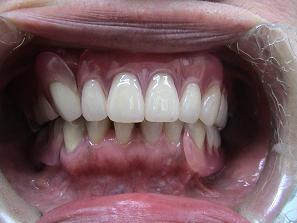

【症例 2】 11歯欠損 (51才,女性)

1.

術前のお口の状態です